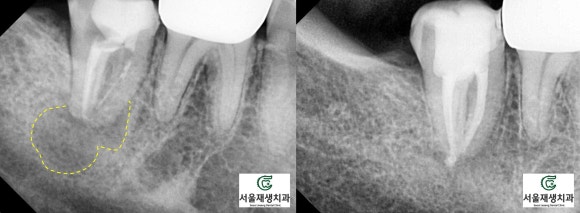

좌측은 2021년 봄, 치료를 시작했을 때,

우측은 2022년 초 치료가 마무리되었을 때 찍은 사진입니다.

치료 완료 당시 아주 적게 남아있던

뿌리 끝 염증이 세월의 흐름과 함께

모조리 말끔하게 사라진 모습입니다^^

뿌리 끝에 드리워져있던

약간의 검은 그림자가

말끔하게 사라진 것을 확인할 수 있습니다.